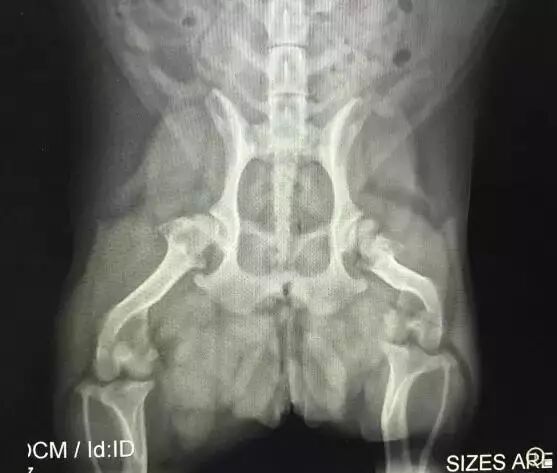

当然你可以说这是一般动物的屁股,不是柯基的呀——那我们来看两张柯基的X光照片吧!

柯基屁股的X光片。图片:mycorgi.com

我知道你可能没看懂,别着急,X光片很容易看的!在X光片中,密度越高的地方颜色越浅,譬如说骨头就接近雪白;而密度越低的区域颜色越深,空气在X光片中应该是黑色的。然后,让我们来找一找,柯基的屁股里有大量深色区域吗?并没有!